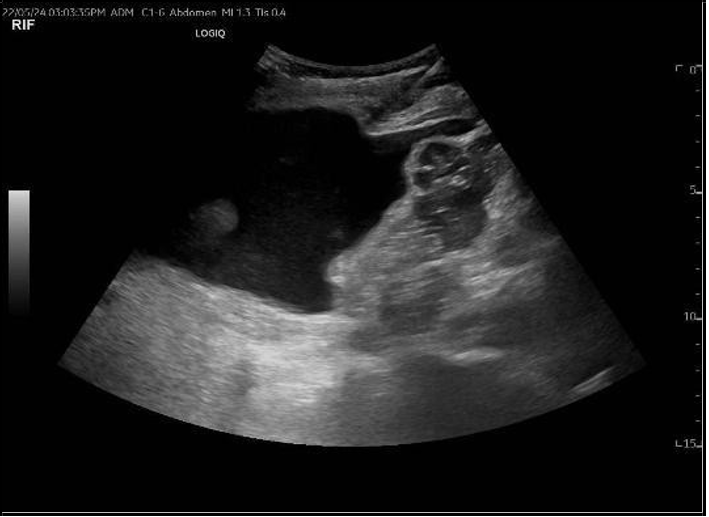

Follow-up graft ultrasound revealed a marked increase in peri-graft fluid collection, expanding from 74 mL to 267 mL, suggestive of a postoperative hematoma or lymphocele [Figure 2]. Following surgical team consultation, the patient was admitted for blood pressure control, red blood cell transfusion, and close monitoring of renal function. After receiving four units of packed red blood cells, her hemoglobin stabilized at 7.4 g/dL, but creatinine continued to rise, reaching 155 µmol/L, with a urine albumin-to-creatinine ratio (ACR) of 762 mg/g.

(A)

(B)

Figure 2: (A) Ultrasound Doppler of renal transplant showing perigraft heterogeneous fluid collection measuring 4.0 × 5.2 × 6.6 cm (74 mL) (B) Left lower quadrant collection measuring 8.6 × 4.8 × 12 cm (267 mL).

On May 21, 2024, the patient was readmitted following two days of anuria due to a blocked nephrostomy tube. Ultrasound evaluation revealed that vascularity within the renal graft remained patent. However, there was a notable progression of the perigraft fluid collection, which had increased substantially to 849 cc from a previous measurement of 30 cc. Additional findings included moderate abdominal ascites and moderate hydronephrosis.

To address the obstruction, a nephrostomy tube exchange was performed, and fluid was drained from the perigraft collection (infected urinoma) [Figure 6]. Drainage cultures subsequently tested positive for ESBL-producing Escherichia coli. The patient was treated with meropenem in response to this infection. Following successful resolution of the infection, the patient underwent cystoscopy that showed complete occlusion of transplanted ureter, then she underwent surgery involving ureter-to-ureter anastomosis. In the postoperative period, the patient experienced additional episodes of urinary tract infection. The causative organisms included Pseudomonas aeruginosa, Klebsiella pneumoniae, and Enterobacter cloacae. All pathogens identified were sensitive to cefepime, allowing for targeted antimicrobial therapy and effective management of these recurrent infections. Subsequently, both the DJ stent and nephrostomy tube were removed.

Figure 6: A) nephrostomy tube exchange, B) ultrasound guidance collection drainage